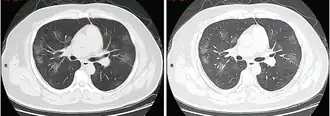

КТ грудной клетки иногда может помочь идентифицировать и охарактеризовать патологию лёгких и дать неспецифические результаты при инфекции COVID-19. Систематический обзор результатов компьютерной томографии грудной клетки у 919 пациентов описал типичное раннее проявление COVID-19 как «двустороннее мультилобарное помутнение матового стекла (GGO) с периферическим или задним распределением».[19] Одно исследование показало, что чувствительность КТ к инфекции COVID-19 составила 98 % по сравнению с чувствительностью ОТ-ПЦР на 71 %; однако это было сделано в китайской провинции Ухань и не подлежит обобщению.[20] Наиболее распространёнными результатами компьютерной томографии были двустороннее затухание матового стекла (пятнистое или рассеянное) с субплевральным доминированием, сумасшедшей укладкой и консолидацией на более поздних стадиях.[21] Эти данные являются неспецифичными и обнаруживаются также при других типах пневмонии. Небольшое исследование показало, что китайские рентгенологи продемонстрировали чувствительность 72-94 % и 24-94 % в дифференцировании COVID-19 от других типов вирусной пневмонии с использованием компьютерной томографии.[22] Ни одно исследование ещё не подтвердило точность и дискриминационную ценность компьютерных томографий, чтобы отличить COVID-19 от других вирусных пневмоний. Поэтому CDC не рекомендует КТ для первоначального скрининга, как подчёркивалось в звонке COCA в четверг, 5 марта. Люди с подозрением на COVID-19 должны проходить ОТ-ПЦР, которая является наиболее специфическим тестом.[23]

Типичные результаты компьютерной томографии

Компьютерная томография стадии быстрого прогрессирования